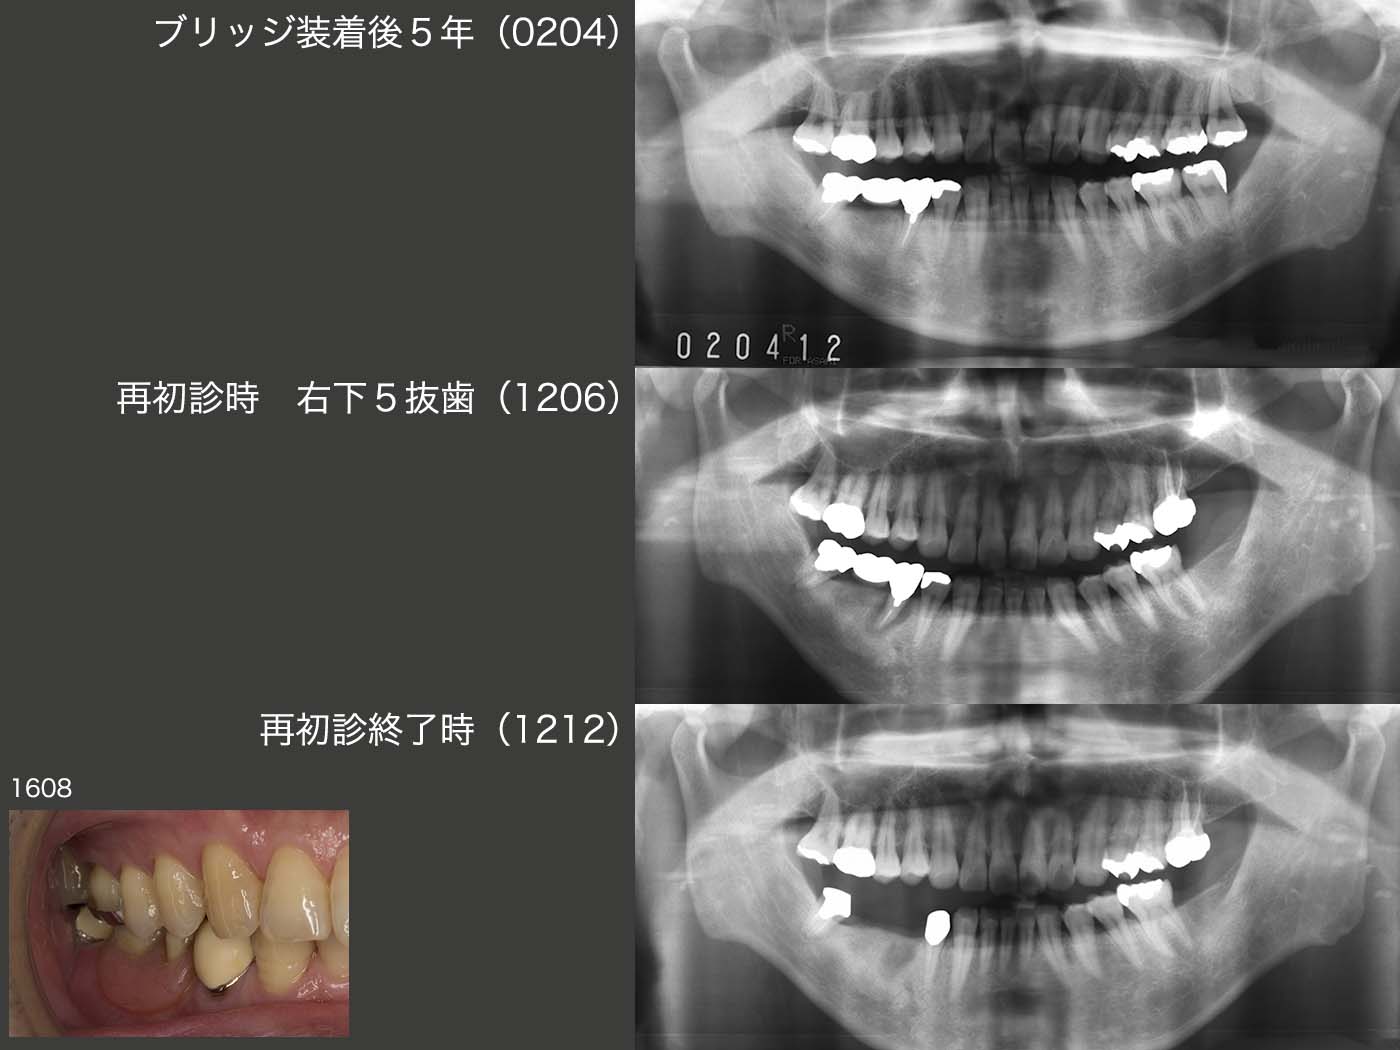

1996年初診,40歳男性.97年に右下⑦6⑤のブリッジを作り直した.特に問題なく経過したが,2012年,ブリッジ装着後15年で右下5に歯根破折が生じた.ブリッジの支台歯が無髄歯の場合に,歯根破折が生じる頻度が高い.

上段のパノラマX線写真は2002年4月,ブリッジ装着後5年の状態である.この時は,大臼歯部において咬合支持数の多い左側で主に咀嚼していたと思われる.05年に左側の上下7を歯周病で抜歯しているが,左側咬みが大きな要因の一つと思われる.中段は12年6月の状態.左側の上下7を抜歯してから,右側で咀嚼する頻度が増し,右下5の歯根破折に繋がったと思われる.なお,左下のスライドは,16年8月の状態.特に順調に経過しているが,つぎは,右下7に問題が生じる可能性が高いと危惧している.

2017年5月に右下7に歯根破折が生じ,抜去した.右下3にクラスプを付与していたため,右下7の外冠を人工歯として増歯するだけの改変で済んだ.